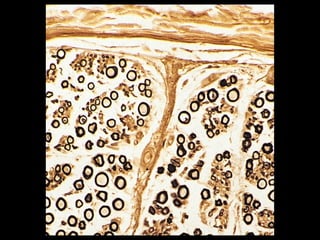

Merkel ending

 Nerve endings are

attached to Merkel

cells

 Merkel cells –

modified epidermal

cells located in skin

 Mechanoreceptors –

sensitive to touch